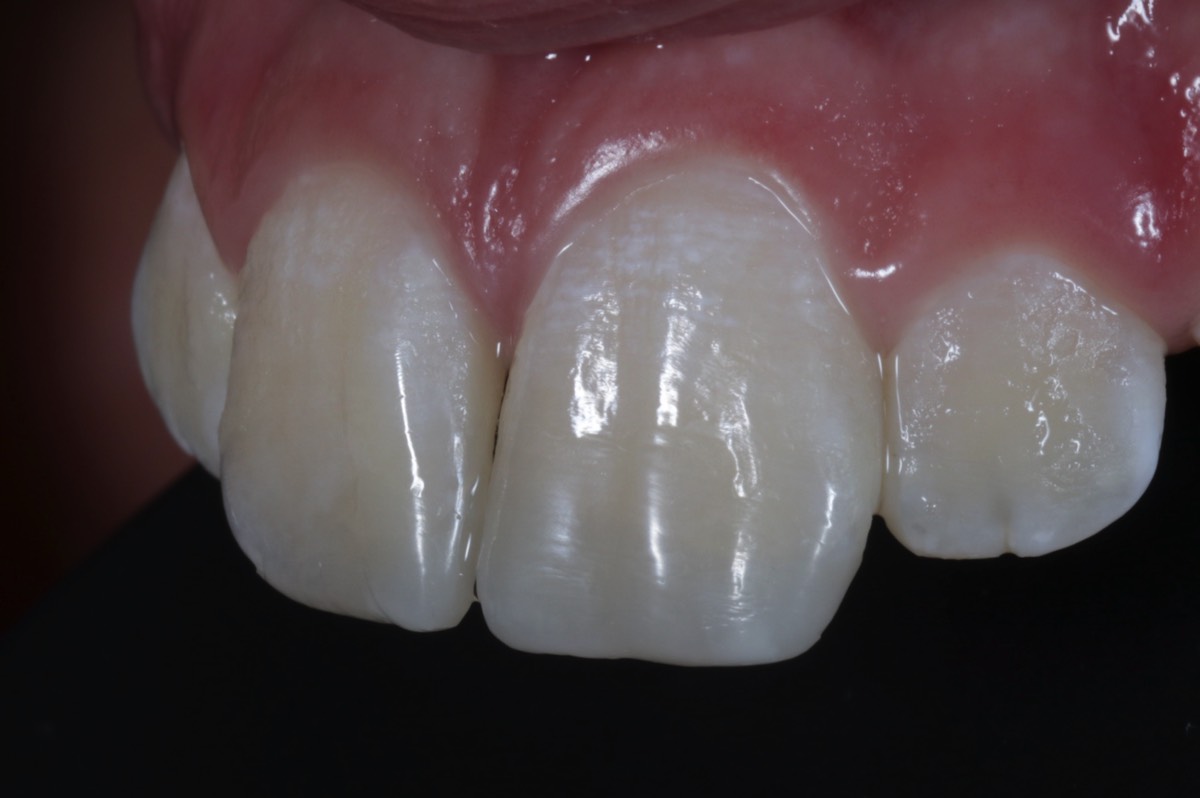

Schöne Zähne und gesundes Zahnfleisch sind die Basis für ein schönes Lächeln. Wir bieten Ihnen mit non- und minimalinvasiven Methoden eine Verbesserung der Funktion und der Ästhetik Ihrer Zähne.

Karies ist eine der häufigsten Zivilisationserkrankungen der Welt. Eine rechtzeitige und minimalinvasiver Behandlung ist das A und O für einen langfristigem Zahnerhalt. Moderne Materialien und ausgefeilte Techniken ermöglichen eine naturgetreue und minimalinvasive Rekonstruktion der kariesgeschädigten Zähne mit einer zahnfarbenen, keramikhaltigen Kompositffüllung.